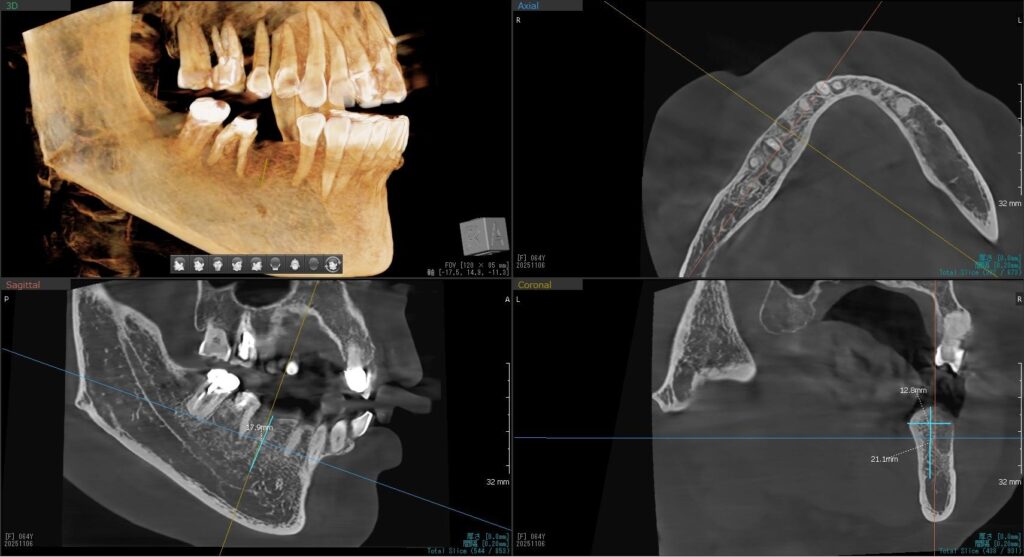

ドリルの先端を細い物から徐々に大きい物に変えながら、植立するインプラント体のネジの部分を除いた胴の部分の太さに合わせた大きさの穴を開けていきます。

開けた穴に、専用道具を使ってネジを締めるように長さ2センチ程のインプラントを骨に埋め込んでいきます。